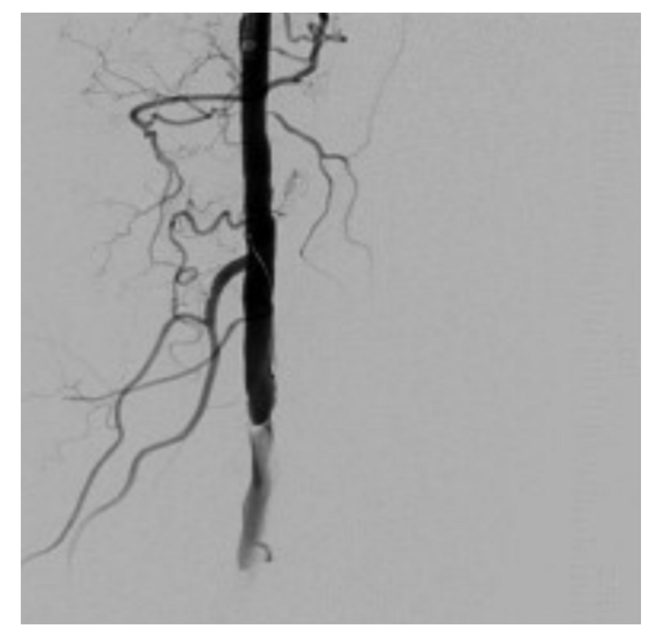

A 6F 70 cm sheath was advanced to the proximal left popliteal artery via contralateral femoral access. An .014-inch Luge wire (Boston Scientific) with support of a 1.2 mm over-the-wire Mini Trek balloon (Abbott Vascular) was advanced through the dissection plane into the left anterior tibial artery. Distal injection confirmed intraluminal crossing. The balloon was removed, a SpiderFX (Medtronic) distal protection device was placed in the distal popliteal artery and optical coherence tomography (OCT) (Abbott Vascular) imaging was performed (Figure 4A-C). OCT images demonstrated an intimal tear of the left popliteal artery and very mild atherosclerotic disease. A 6 x 40 mm Chocolate balloon (Medtronic) was advanced to the site of the dissection and the lesion was dilated to 4 atmospheres (atm) for 3 minutes. Post PTA angiographic images showed TIMI-3 flow without evidence of dissection, perforation, or embolization (Figure 5). To our knowledge, there are no reported cases or series using OCT to confirm popliteal artery dissection.

Nine months later, a follow-up arterial duplex ultrasound demonstrated the presence of normal triphasic flow in the proximal and distal popliteal artery with preservation of the lumen (Figure 6). The patient remains active and free of symptoms.